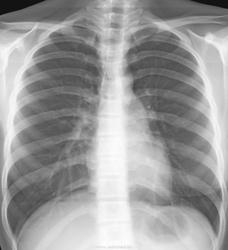

ЦФОГК, девушка 16 лет

Плановая флюорография школьников. После была дообследованна и оказалось.....   . Какие мнения будут уважаемые коллеги?

В глаза бросалась доп тень правее корня правого легкого.  После была правая боковая проекция (лаборант срезал верхушку - поэтому не буду его выкладывать с браком), на которой доп теней не наблюдал, во время выяснения анамнеза жизни девушки заметил что у нее длинные волосы в виде двух косичек с резинками на концах, пересняли в прямой проекции в моем присутствии как надо было - с убранными волосами. вот что получилось в итоге:

справа в средних отделах хрень какая-то. ТБЦ?

В мягких тканях левой надключичной области кальцинат (не исключается кальцинированный лимфоузел). В органах грудной клетки патологии я не нашёл. А можно анамнез поподробнее?

Я, видимо, дура. Норму бы написала. В крайнем случае получше бы разглядела передний отрезок 4 ребра справа.

Жаль нет боковой... Справа анамальная сосудистая тень связанная с корнем, похоже АВМ. Слева над ключицей вероятно коса.

Рек. вызвать рентгентехника. Артефакт.

Волосы.

Аномальный дренаж легочных вен?